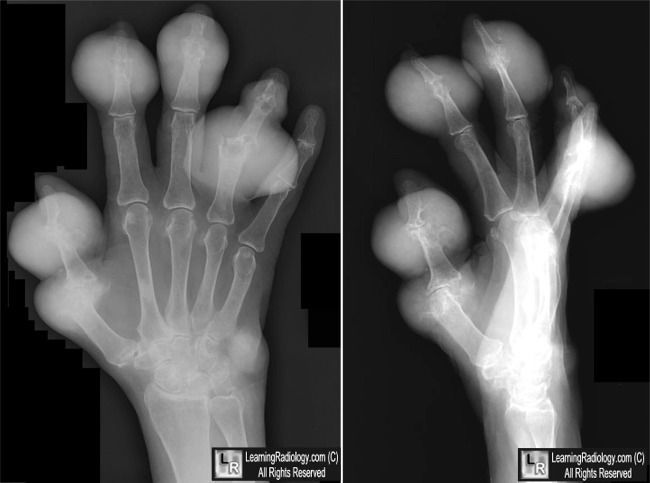

Chronic gout can lead to deposition of calcium urate crystals in soft tissues. These deposits are called tophi. Punched out erosions may also be seen in case of gout. Reference: http://learningradiology.com/archives2010/COW%20423-Gout%20hand/goutcorrect.htm Image via: http://learningradiology.com/archives2010/COW%20423-Gout%20hand/goutcorrect.htm

Punched out ,lytic lesion with overhanging edge and sclerotic border is characteristic of chronic Gout